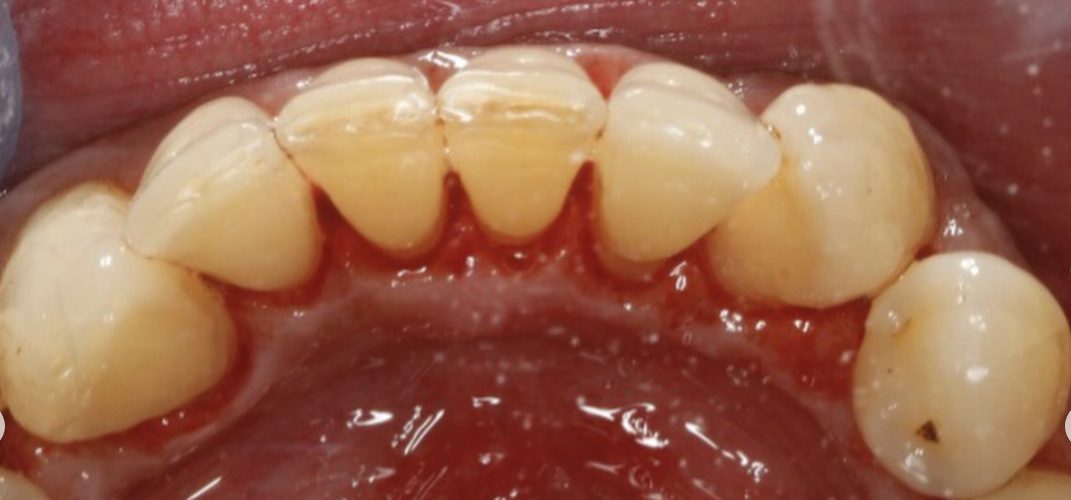

- Remove staining and discolouration caused by smoking or by drinking drinks such as red wine, tea and coffee etc

- Thoroughly remove dental plaque

- Restore white teeth

Before and After Photos